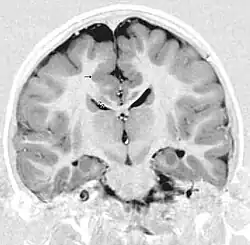

Gray matter heterotopia

Gray matter heterotopia is a neurological disorder caused by gray matter being located in an atypical location in the brain.[1]

Gray matter heterotopia are common malformations of cortical development known as neuronal migration disorders. Heterotopias are classed in two groups: nodular and diffuse. Nodular types are subependymal and subcortical; diffuse types are termed band heterotopias. Affected patients are generally divided into three groups, depending on the location of the formation: subependymal, subcortical, and band heterotopia. In addition, especially with heterotopia that are genetically linked, there are sex differences. Men seem to develop more severe symptoms than women with similar formations.

Periventricular means beside the ventricle, while subependymal (also spelled subepydymal) means beneath the ependyma; because the ependyma is the thin epithelial sheet lining the ventricles of the brain, these two terms are used to define heterotopia occurring directly next to a ventricle. This is by far the most common location for heterotopia. Patients with isolated subependymal heterotopia usually present with a seizure disorder in the second decade of life.

Subependymal heterotopia present in a wide array of variations. They can be a small single node or a large number of nodes, can exist on either or both sides of the brain at any point along the higher ventricle margins, can be small or large, single or multiple, and can form a small node or a large wavy or curved mass.

Detection of heterotopia generally occurs when a patient receives brain imaging—usually an MRI or CT scan—to diagnose seizures that are resistant to medication. Correct diagnosis requires a high degree of radiological skill, due to the heterotopia's resemblance to other masses in the brain.